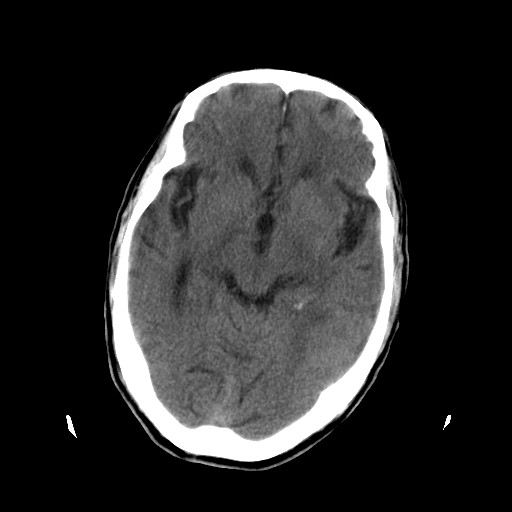

患者,男,70岁,清晨(10小时前)无法自行起床,家人无法唤醒,现昏迷,大小便失禁

左颞枕叶交界区可见类圆形高密度区,边缘可见环形更高密度影,并夹杂有点状钙化影,占位效应明显,未见明显水肿影,考虑脑膜瘤出血

肿快呈以等密度为主的等高密度影,占位效应不是很明显,只是左枕角受压,肿块内侧似有低密度改变.

左颞枕叶交界区可见类圆形高密度区,边缘可见环形更高密度影,侧脑室后角明显受压而周围未见明显水肿.考虑脑膜瘤伴出血可能性大不排外血管畸形.建议mr进一步检查.

左侧颞枕叶交界区见类圆型等高密度混杂影,边缘可见高密度影环绕,同侧侧脑室后脚受压变形,周边围见明显水肿影. 结论:脑膜瘤首先考虑.